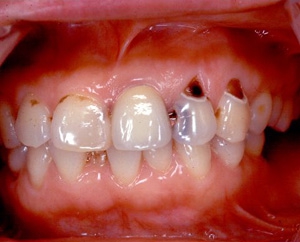

インセラム(オールセラミック)症例①

治療前治療前インセラム(オールセラミック)冠による修復。 主訴は前歯が汚い 金属を使わないオールセラミックでの治療を勧めた。 術前 治療後治療後術後